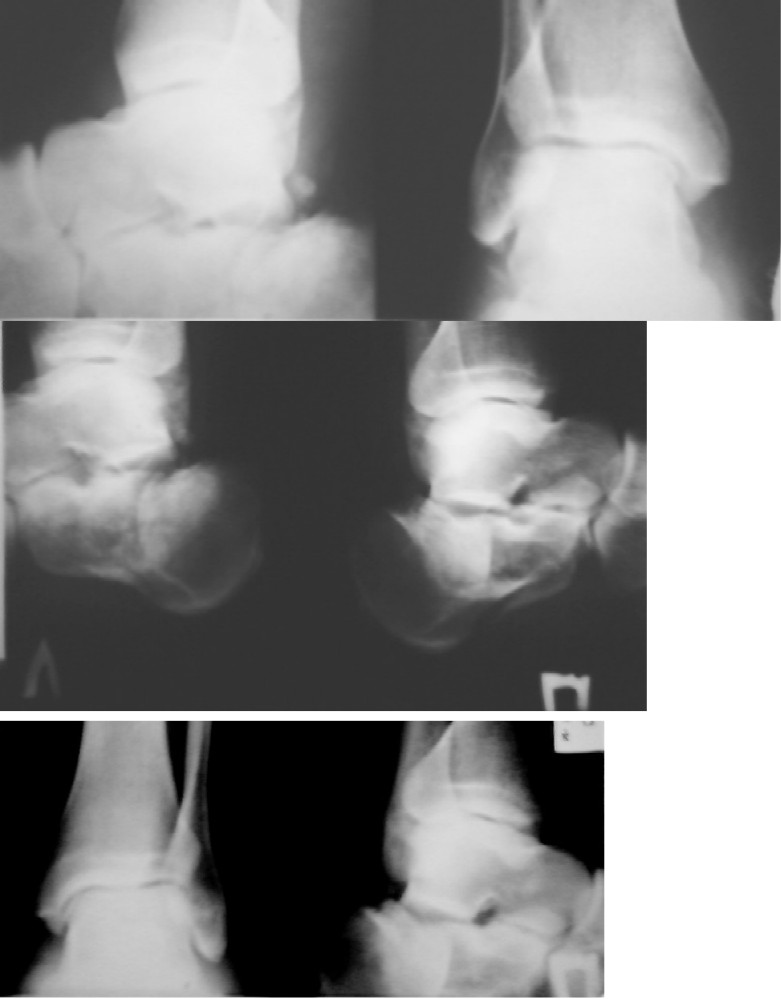

Травма случилась около 16 часов, но только на следующий день к вечеру, по моему настоянию поставили гипс или лангет, ну типа временной конструкции.Смотрю я на свои рентгеновские снимки и не вижу где переломы, нет в правой ноге вижу, а в левой нет. Да и с левой ноги отек довольно начал спадать. Может всетаки диагноз не вполне точный.А про способ лечения перелома пятки аппаратами Илизарова вообще очень много сомнения, ведь за границей этот способ не применяют с 1965 года.Уважаемые форумчане-доктора посмотрите мои снимки и скажите свои точки зрения.С уважением Александр Блинов С-Петербург 45 лет.

• Кликните для загрузки файла Микс.jpg

61KB (62784 bytes)

Переломы отчетливо видны. Насчет "за границей этот способ не применяют с 1965 года" - это просто чепуха несусветная, в то время метод Илизарова в СССР-то не везде еще применялся. А за границей, да при переломах пятки, его стали применять только лет 10-15 назад.